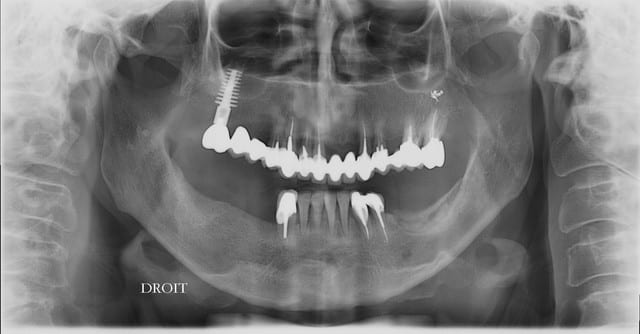

panoramique et photo pas de suite post op pas d'hematome, pas de douleur YESSSS

implants dans 5 mois si tvb

bridge de fou (33-37) qui est tombé il y a une semaine.

si possible 3 implants et le patient est ok pour expansion, reste plus qu'à voir pour le planing...